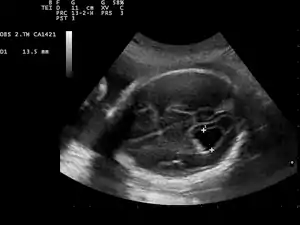

Ventriculomegaly is a brain condition that mainly occurs in the fetus when the lateral ventricles become dilated. The most common definition uses a width of the atrium of the lateral ventricle of greater than 10 mm.[1] This occurs in around 1% of pregnancies.[2] When this measurement is between 10 and 15 mm, the ventriculomegaly may be described as mild to moderate. When the measurement is greater than 15mm, the ventriculomegaly may be classified as more severe.[3]

This diagnosis is generally found in routine fetal anomaly scans at 18–22 weeks gestation. It is one of the more common abnormal brain findings on prenatal ultrasound, occurring in around 1–2 per 1,000 pregnancies.[4] In many cases of mild ventriculomegaly, however, there is resolution of ventriculomegaly during the pregnancy.

Although evaluation of lateral ventricles dimensions is decisive for establishing a diagnosis of ventriculomegaly, the shape of the ventricular system, including that of the frontal horns, is also important.[10]